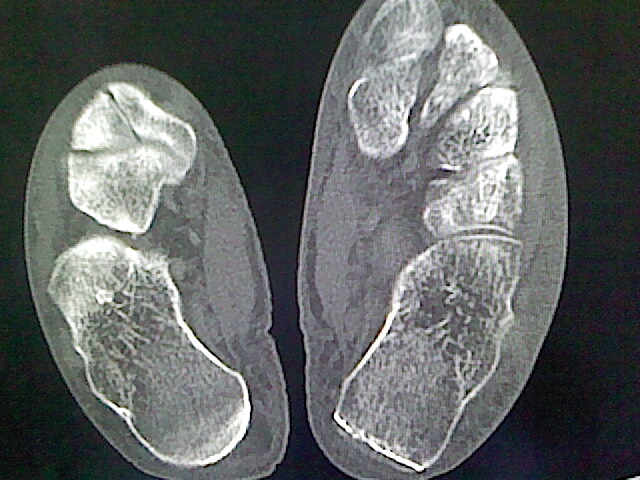

本例骨质改变主要表现为滑膜或韧带区的骨侵蚀融解(胫腓联合区骨质破坏无硬化边),距骨后部骨质破坏区有硬化边及死骨样改变.所以,本例考虑关节结核可能性大,绒毛膜结节性滑膜炎多发于中年,且极少见于膝髋以外的关节,骨质硬坏也以压陷吸收为主,有明显的硬化边,骨膜增生呈结节状(可以mr鉴别),所以本例暂除外.

另不除外可引起相似表现的其他炎症如布氏杆菌性关节炎等